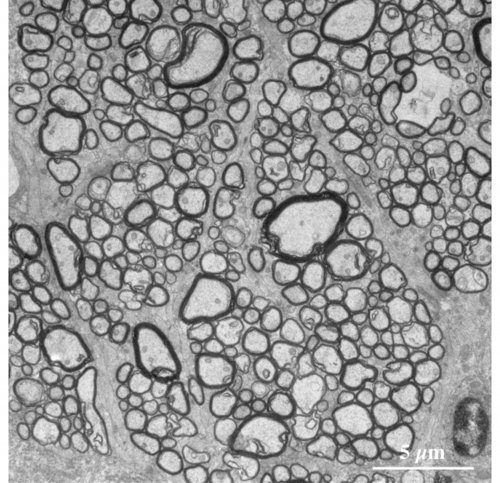

【 薄さ70 - 80 nm 超薄切片の透過型電子顕微鏡画像 】

Transmission electron microscopic image of 70 - 80 nm ultrathin section

視神経を構成する有髄神経線維 myelinated nerve fibers の横断面